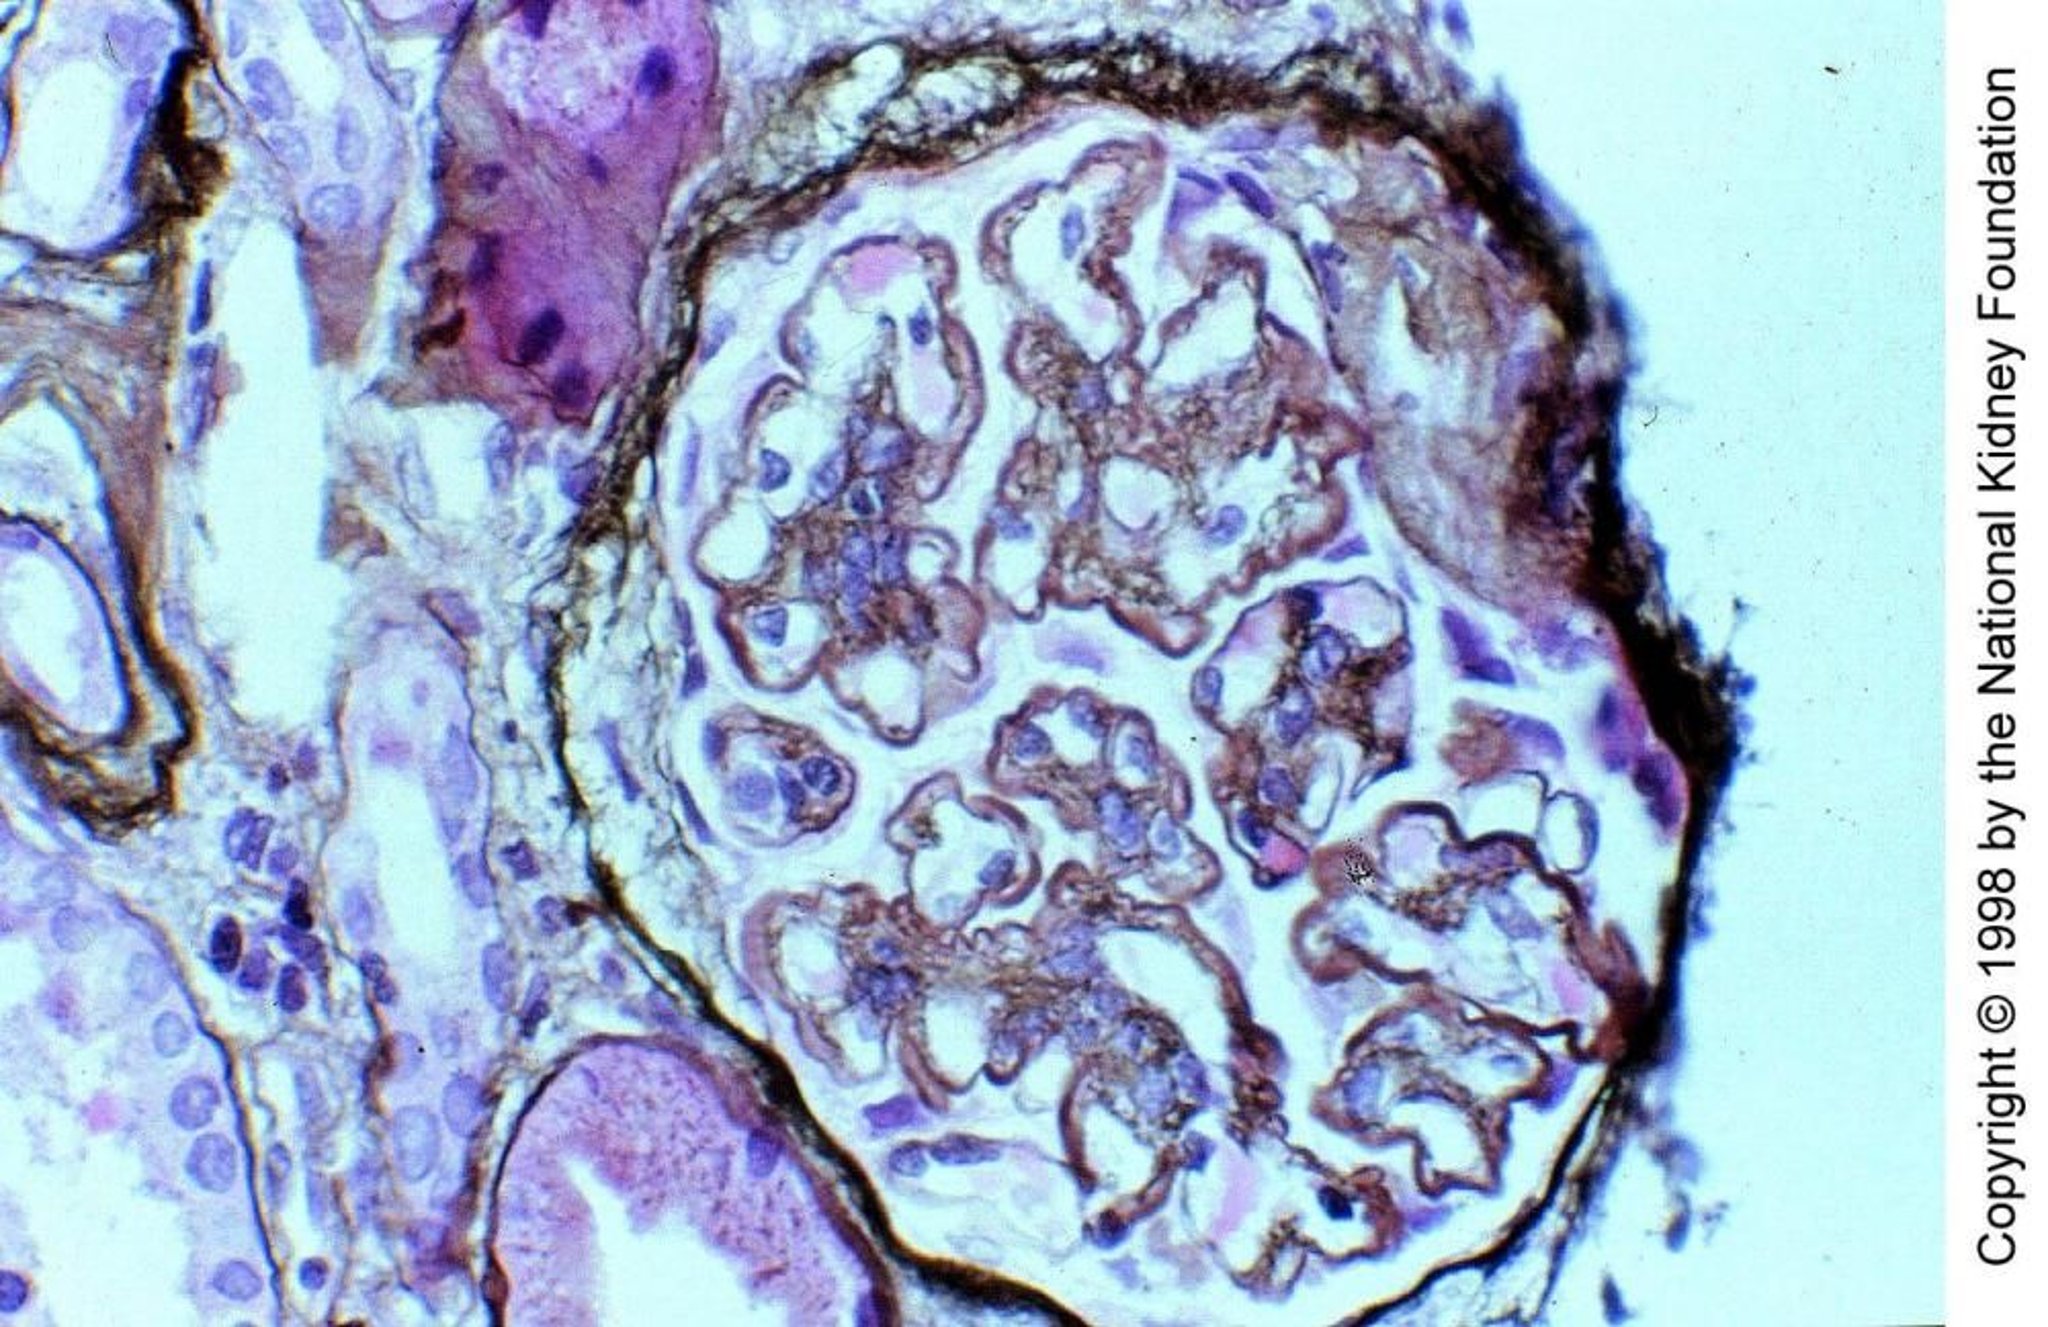

Glomerulonefritis membranoproliferativa, mediada por complemento

En la glomerulonefritis membranoproliferativa (GNMP) de tipo II mediada por el complemento, el factor nefrítico C3, un autoanticuerpo IgG que funciona como properdina al escindir directamente C3 a C3b, activa el complemento a través de la vía alternativa dentro de las paredes capilares glomerulares y el mesangio. Los depósitos de C3 reemplazan parcialmente la lámina densa de la membrana basal, lo que le da un aspecto engrosado y distintivo en forma de cinta (tinción de plata de Jones, ×400).

Image provided by Agnes Fogo, MD, and the American Journal of Kidney Diseases' Atlas of Renal Pathology (véase www.ajkd.org).